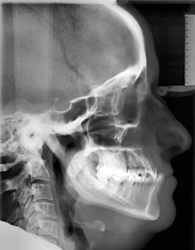

Kieferorthopädisch-kieferchirurgische Kombinationsbehandlungen

Wenn nicht nur die Zähne, sondern auch der Oberkiefer oder der Unterkiefer verändert werden müssen, so kann dies mit Spangen nur während der Wachstumsphasen gemacht werden.

Ist das Wachstum beendet, so kann diese Kieferveränderung nur operativ korrigiert werden.

Der Kieferorthopäde verschiebt die Zähne, der Kieferchirurg operiert den Kiefer. Anschließend sorgt der Kieferorthopäde wieder dafür, dass alles zusammenpasst.